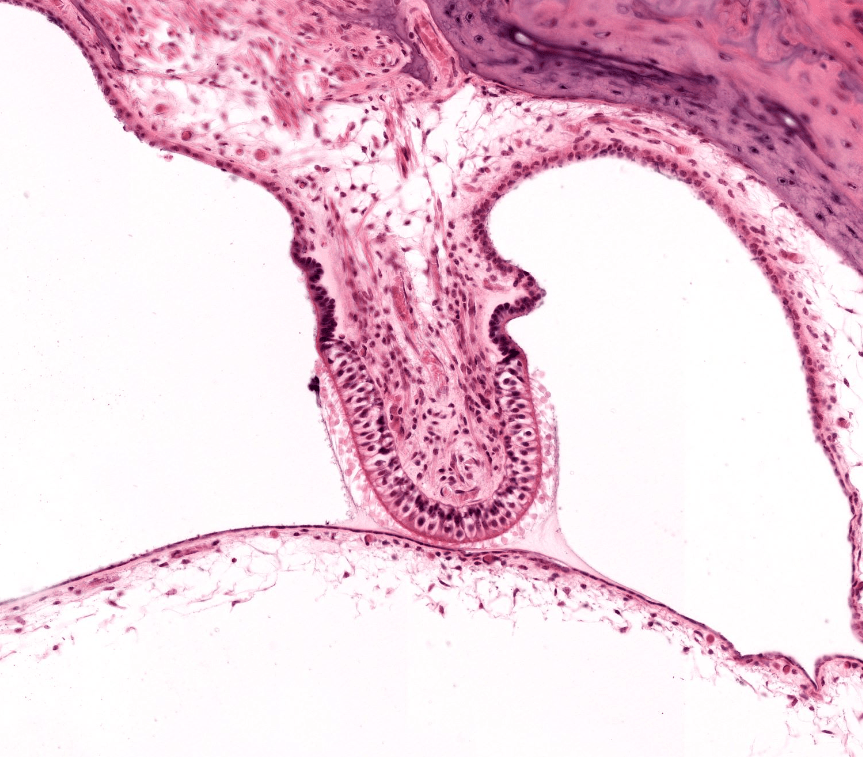

Órgano de Corti, HyE.

Procesamiento; Laboratorio de Histología del DBCT, FACMED UNAM.